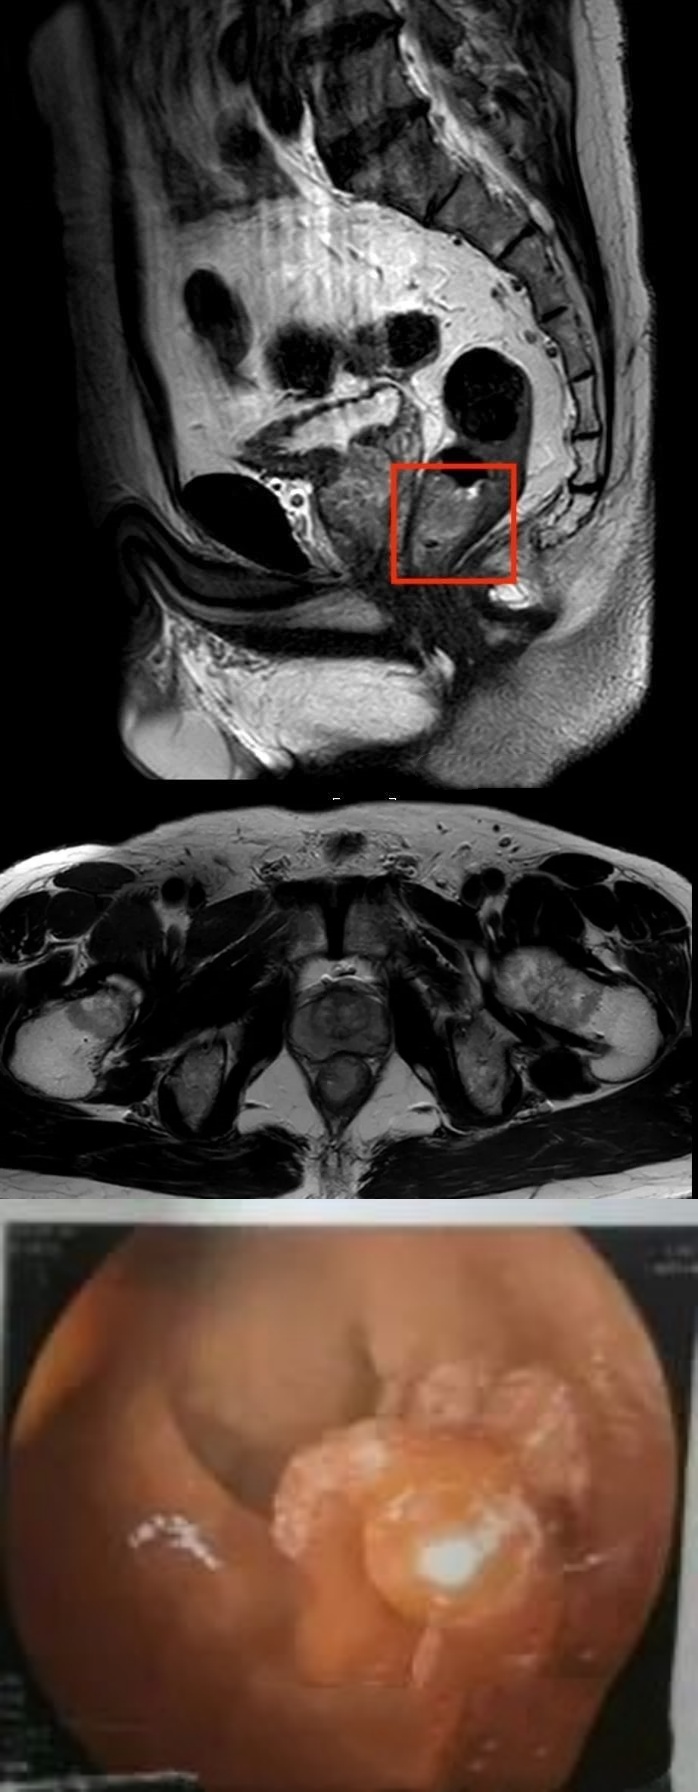

1个月前,张先生确诊为超低位直肠癌,肿瘤下缘距肛门仅3.5厘米。多家医院就诊后给出相同结论:必须行传统Miles手术(腹会阴联合直肠癌根治术),这意味着永久性切除肛门,余生需依靠腹部造瘘生活。患者痛苦与不甘,辗转就医,最终来到上海市第六人民医院(简称“六院”)胃肠外科求治。

超低位直肠癌保肛手术历来是外科领域的“珠峰”——肿瘤位置越低,保肛难度越大。国际指南中,肿瘤距肛门<5cm以下,就已经是超低位保肛的范畴。而张先生的肿瘤距肛门3.5cm,加上男性骨盆狭窄、前列腺肥大、肿瘤位于直肠前壁的解剖特点,传统手术难以在狭小空间灵活操作,稍有不慎就可能损伤神经、血管甚至肿瘤残留。即便是成熟的腹腔镜技术在这种情况下也力不从心。

面对这么复杂的情况,六院胃肠外科王志刚主任团队经过讨论后决定采取机器人辅助,突破人手极限,在骨盆深处精准分离肿瘤;应用NOSES(经自然腔道取标本)技术将肿瘤自盆腔内翻出肛门外;并结合ISR(内括约肌切除)+适型切除,直肠残端与乙状结肠体外吻合。

历经3小时精细操作,肿瘤被完整切除,吻合器在肛门上方2cm成功完成肠道重建。既根治癌症,又保住了肛门!